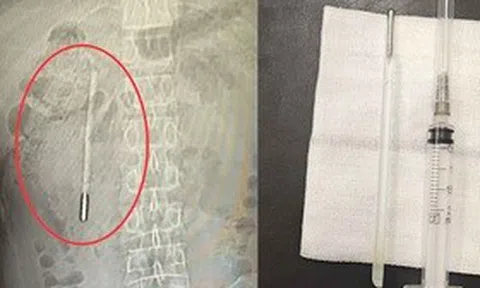

Bác sĩ điều trị của anh cho biết sự ra đi của anh không phải là một sự tình cờ, mà là hệ quả của cơ chế "đốt khô" cơ thể khi uống quá nhiều caffeine và thiếu ngủ. Khi thức khuya làm việc, hệ thần kinh giao cảm bị ép hoạt động quá mức, tiết ra lượng lớn hormone norepinephrine làm co thắt mạch máu và tăng huyết áp.